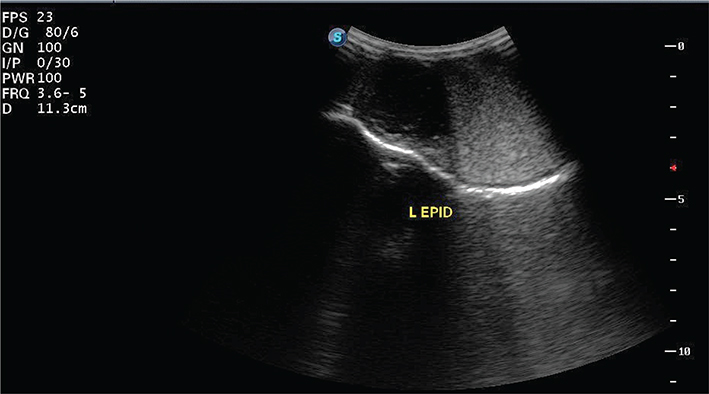

Testes ultrasonography (Sonoscape S8 Exp, 3.2 MHz probe) revealed a parenchyma that was normal, homogeneous, moderate echogenic in appearance; epididymal heads were dilated and predominantly anechoic (Figure 1). Epididymal tails were small and predominantly anechoic. Brucellosis card agglutination test was negative.

Figure 1.

Figure 1. Ultrasonogram of left epididymal head; note anechoic dilation